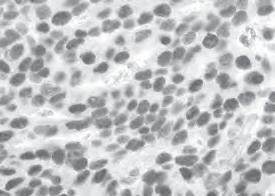

The cells that line the intestines are a crucial interface between the outside world and the human body, but many mysteries remain as to how they work. Research published by an international team led by Hudson Institute investigated so-called Mediator kinases – regulators of gene expression – and discovered that they play an unexpected role in maintaining a proper balance of the different cell populations that make up the intestinal lining. Dr Marius Dannappel and Dr Danxi Zhu, with their mentor Professor Ron Firestein, found

that Mediator kinases also interact with another group of proteins that have been linked to many diseases and cancers. Their findings have wideranging implications for inflammatory conditions affecting the intestine, such as  Inflammatory Bowel Disease (IBD) and cancer.

“We discovered that Mediator kinases play a pivotal role in orchestrating the production of the cells lining the intestinal lumen, particularly for

specialised cell types (Paneth cells, tuft cells and goblet cells) responsible for organising the defence against infection.”

Published in the Journal of Clinical Investigation, October 2022